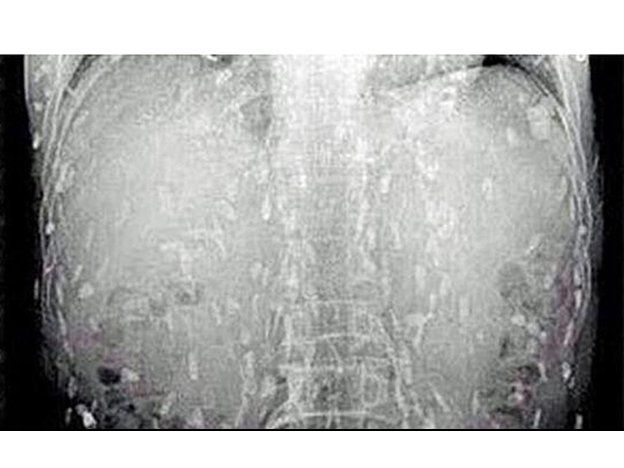

Preocupado, acudió rápidamente al hospital, donde los médicos llevaron a cabo varias radiografías para saber cuál era la causa de su malestar. Al observar las imágenes, la sorpresa fue generalizada entre los profesionales: el paciente tenía todo el interior del cuerpo lleno de pequeños gusanos, los cuales pueden crecer hasta 10 metros dentro del cuerpo.

Los médicos que atendieron al hombre –de la provincia de Guangdong, al este del país-, consideran que el pescado crudo que comió podía estar en mal estado, lo que habría provocado esta infección masiva de parásitos. Aunque en la mayoría de los casos no es mortal, los gusanos se alojan normalmente en el intestino delgado y grueso del ser humano. En ocasiones, puede acabar con la vida de una persona si empieza a 2alimentarse"cerca de los órganos vitales.